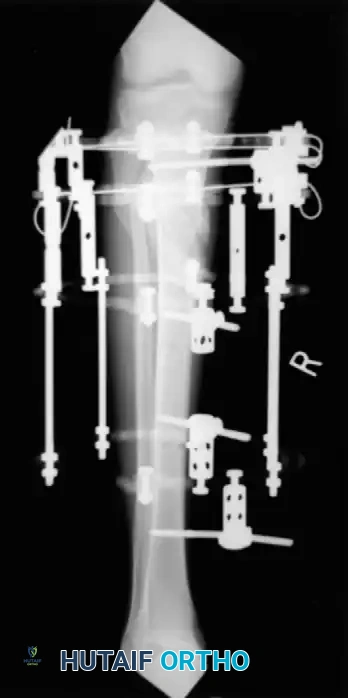

Advanced Surgical Technique: Circular External Fixation

While IM nailing is ideal for diaphyseal fractures, external fixation—particularly circular ring fixators (Ilizarov or Taylor Spatial Frame principles)—is invaluable for severe open fractures, highly comminuted metaphyseal-diaphyseal fractures (AO Type C), and fractures with extensive periarticular involvement.

Step 2: Wire Placement and Diastasis Reduction

At least three or four olive wires are necessary to obtain adequate fixation of the articular surfaces.

- If the distal tibiofibular joint (syndesmosis) has been disrupted, use an olive wire to reduce the diastasis by passing the wire from the fibula across the tibia.

- If the fibula has not been plated, ensure that it is pulled out to its full length and that appropriate rotation is maintained before placing the tibia-fibula transfixation wire.

- Place the final wire—a transverse reference wire—just anterior to the fibula. Pass this wire only through the tibia to ensure that it is perfectly parallel to the joint line, approximately 1 cm proximal to the ankle joint.

Step 4: Symmetrical Tensioning

Proper tensioning of the wires is what provides the circular frame with its unique biomechanical stability (beam loading).

- Tension the opposing olive wires symmetrically using two-wire tensioners.

- Crucial Step: Perform this tensioning strictly under fluoroscopic control. Asymmetrical tensioning can cause unequal compression across fracture lines, leading to iatrogenic displacement or varus/valgus malalignment.

Step 5: Proximal Extension and Shaft Alignment

Once the periarticular block is secured, attention turns to the diaphyseal comminution.

- Attach the distal ring block to the proximal rings using threaded rods equipped with conical washers. These washers allow for multi-planar variability in reducing and maintaining the overall mechanical axis.

- Use the ring at the level of the proximal shaft extension to reduce proximal shaft comminution.

- Use additional olive or smooth wires to manipulate and maintain shaft alignment, effectively "pulling" large butterfly fragments into the construct. Attach these wires to the mid-distal ring and tension them under fluoroscopy so the reduction can be observed in real-time.

Associated Surgical & Radiographic Imaging